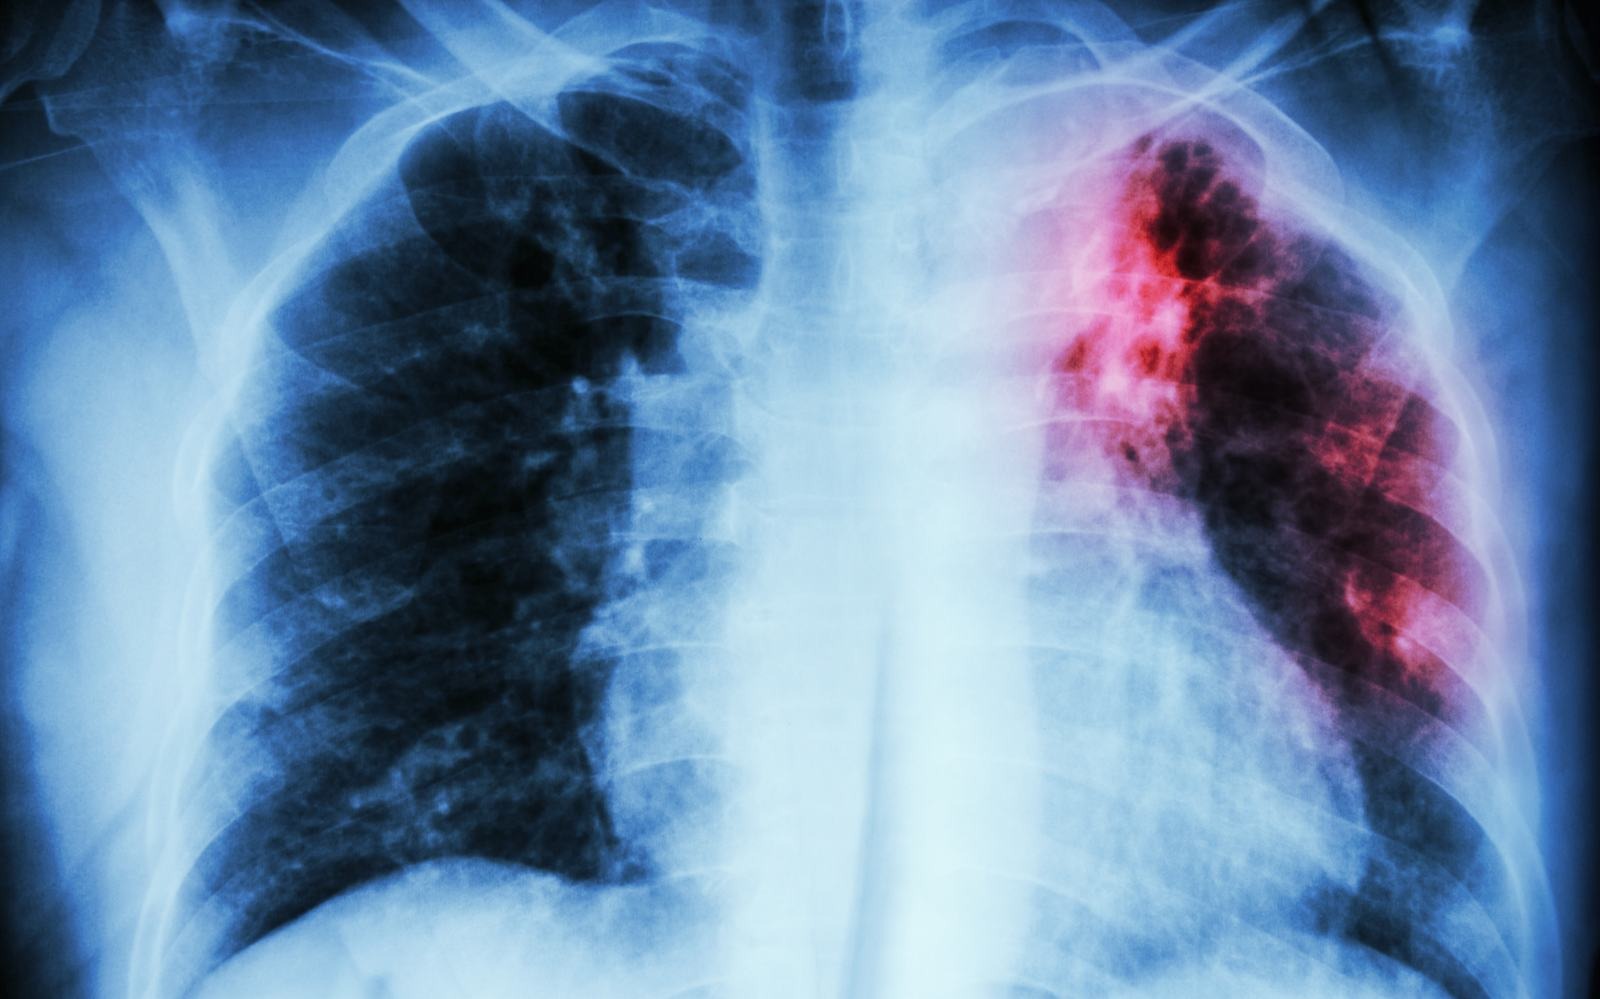

The World Health Organization has been calling for the development of a blood-based triage test for active tuberculosis (ATB) — one that's accurate and cheap enough for use in developing nations where most TB-related deaths occur. Sputum-based tests are typically slow and require infrastructure some local communities in developing regions may not have. Now, a team of researchers have developed a blood-based test, which can be configured into a $2 consumable version that delivers results in 30 minutes.